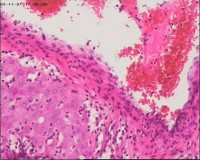

性别

女

年龄

20岁

停经3月,阴道不规则流血7天。

宫刮物

灰白灰红碎组织一堆,大小为7*6*1cm,部分组织呈水泡状

水肿的绒毛和蜕膜,没看到增生的滋养细胞。必要时可做IHC除外部分葡萄胎,并结合临床HCG。

考虑葡萄胎